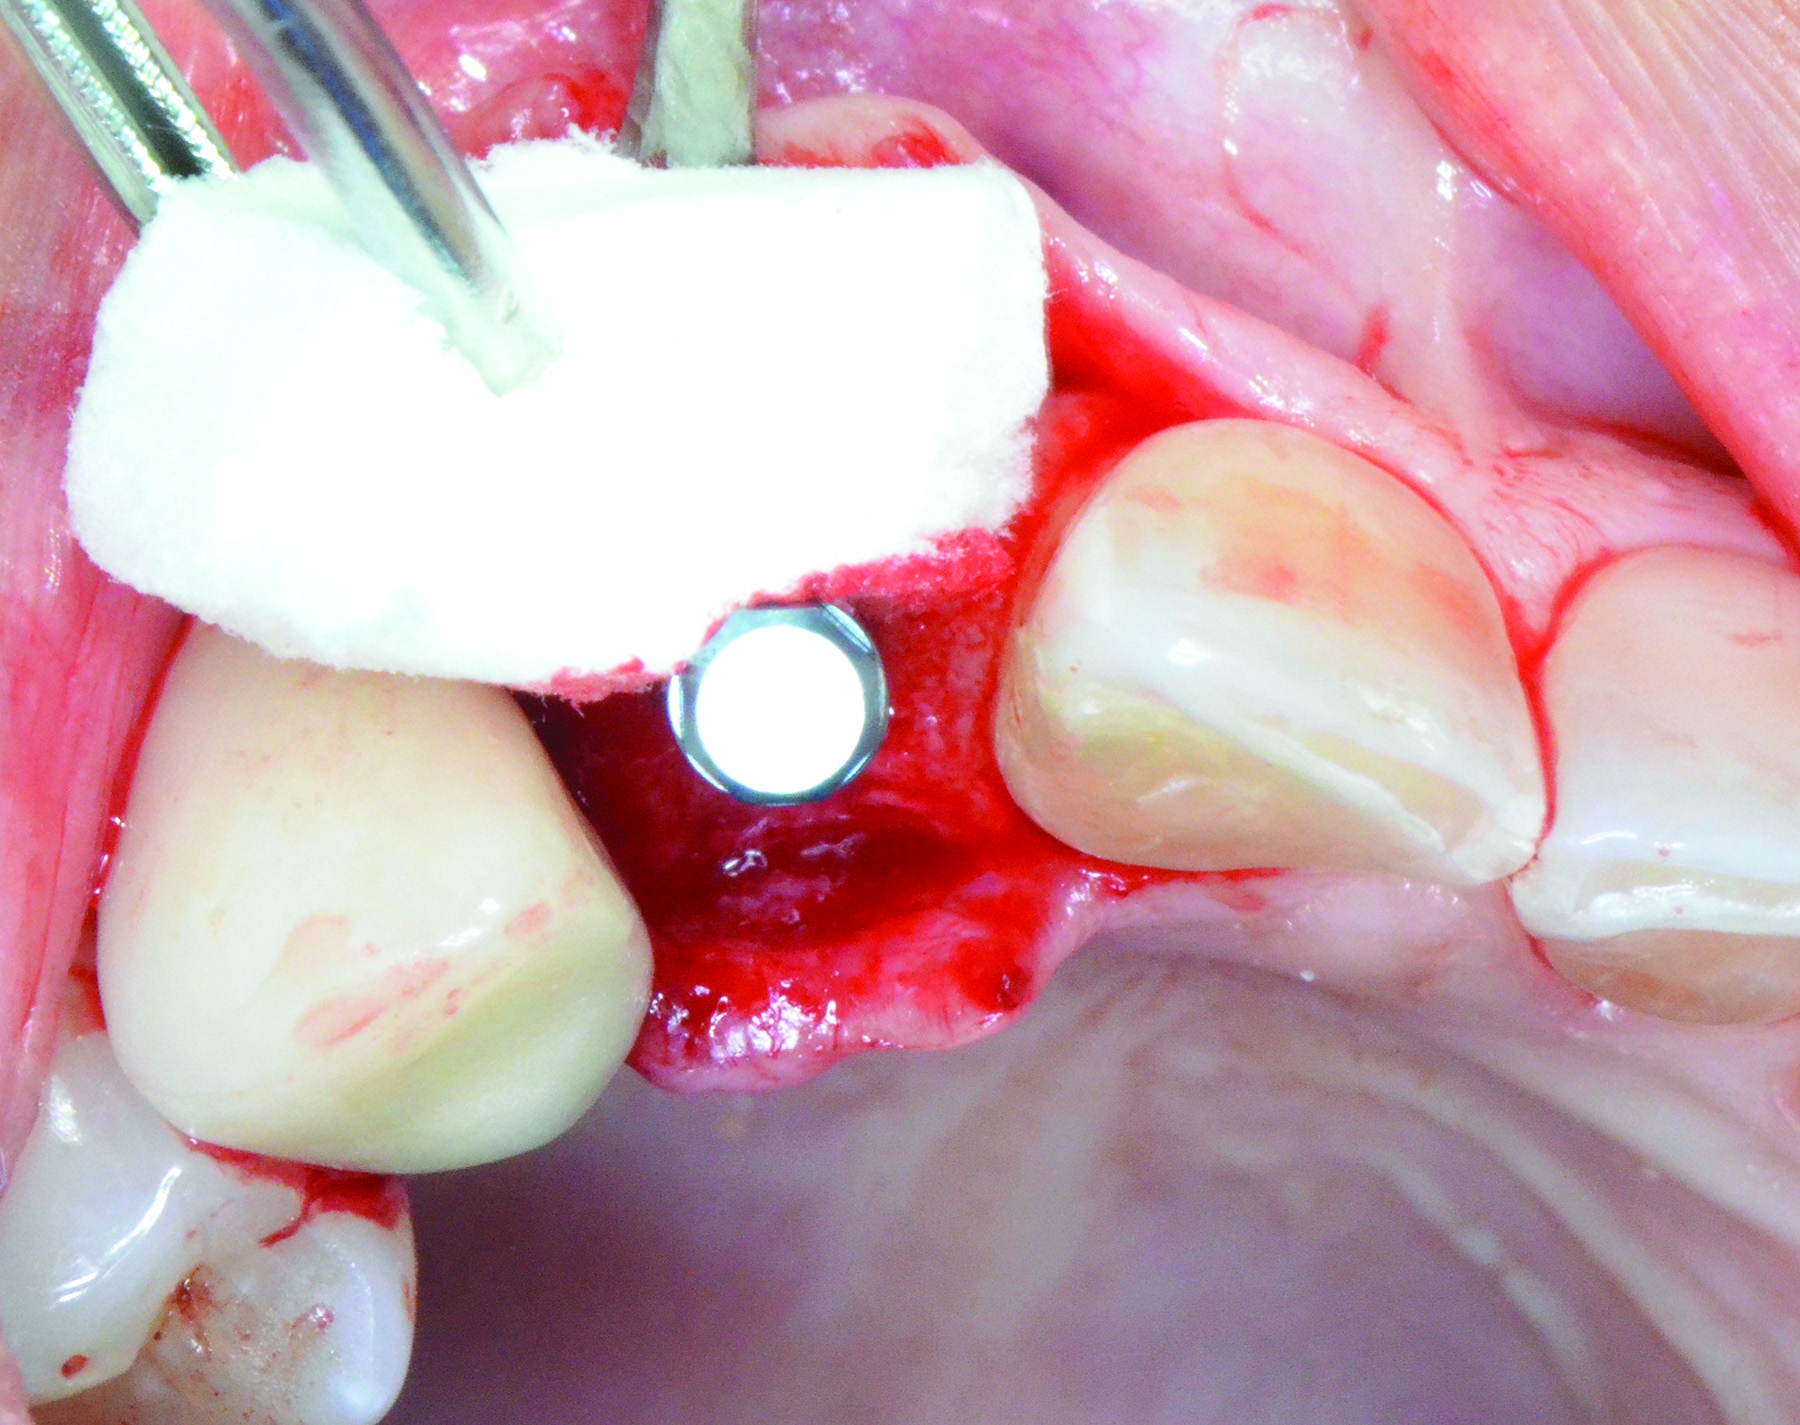

Fig 12 through Fig 14. Example of increasing MT with a roll technique. Fig 12: incision design for implant placement with a healing abutment placement and to enhance MT; the recipient site is prepared on the buccal side; the palatal aspect of the flap will be rolled to the buccal recipient site; Fig 13: insertion of roll of tissue taken from the palatal aspect of the flap; Fig 14: implant placement with healing abutment.